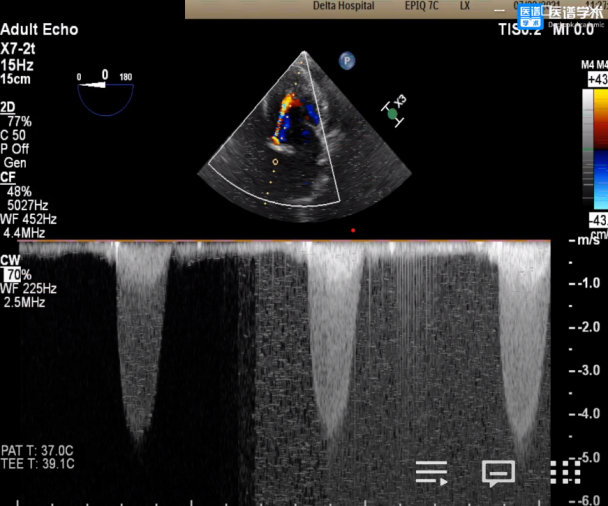

术前平均跨瓣压差66mmHg

术前超声提示左室最大射血速度4.6m/s

超声影像

术后即时数据显示,患者平均跨瓣压差降至6 mmHg,AV前向血流速度降低至1.7 m/s,手术效果非常理想。